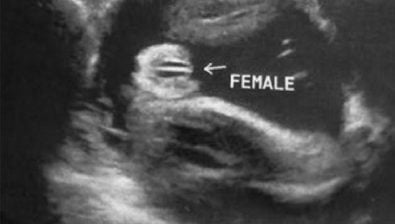

Ultrasound at 34 Weeks